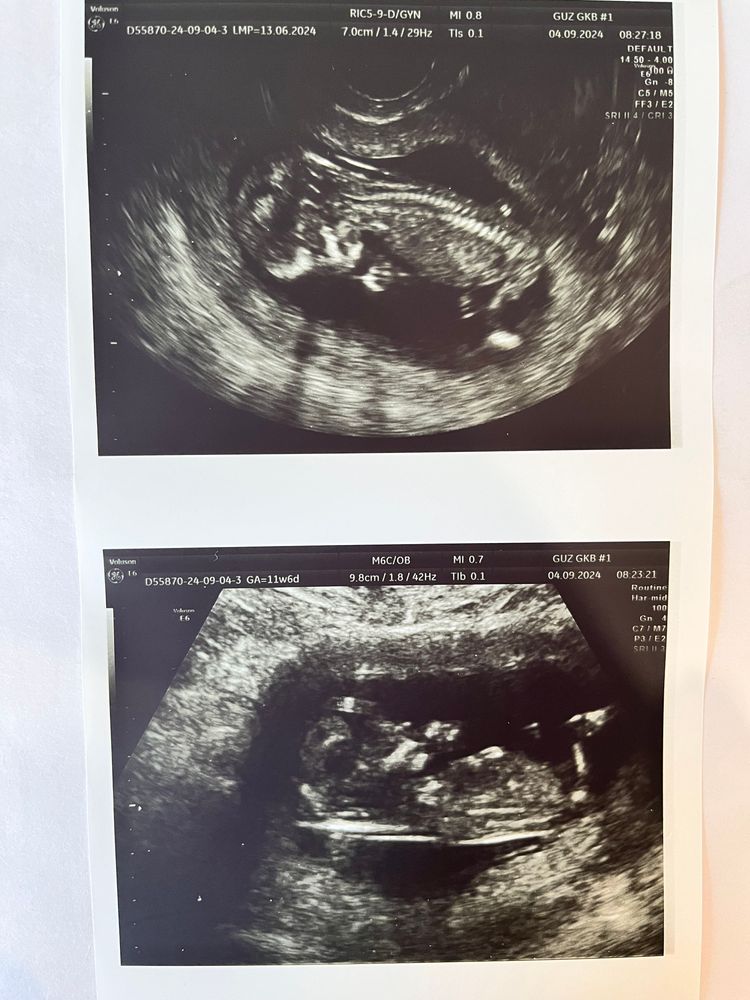

Кто в домике живет? УЗИ первый скрининг

Анализы, скринингиВот и прошли мы первый скрининг❤️

С малышком все хорошо) Нам почти 12 недель.

По размерам опережает на неделю, ктр 65мм(что соответствует 12,6 Нед). бпр=19мм(13 Нед), ОГ=71мм (13нед)

чсс=150уд/мин

Говорят, что опережают обычно мальчики и головастые они 😄 Я про пол спрашивать не стала, дотерпим до второго скрининга. Мы с мужем очень хотим девчулю, у нас есть старший сын, да и вообще у нас в семье одни мальчишки, ни одной девчонки.. Просто до слез мечтаю о девочке🌸Девчата, снимок конечно не очень четкий и удачный, может кто разбирается, как думаете кто в у нас в животике???🙏